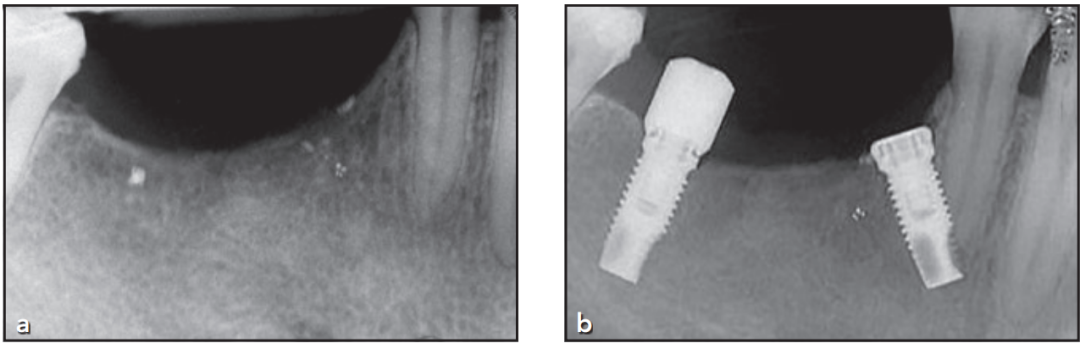

术后2年随访

患者坚持双月维护计划,修复体功能良好,无主观不适主诉。术后4年行锥形束CT(CBCT)检查,影像学评估证实:

种植体周围骨结合状态稳定;

根尖区骨组织持续保持愈合状态;

未发现病理性改变(图4)